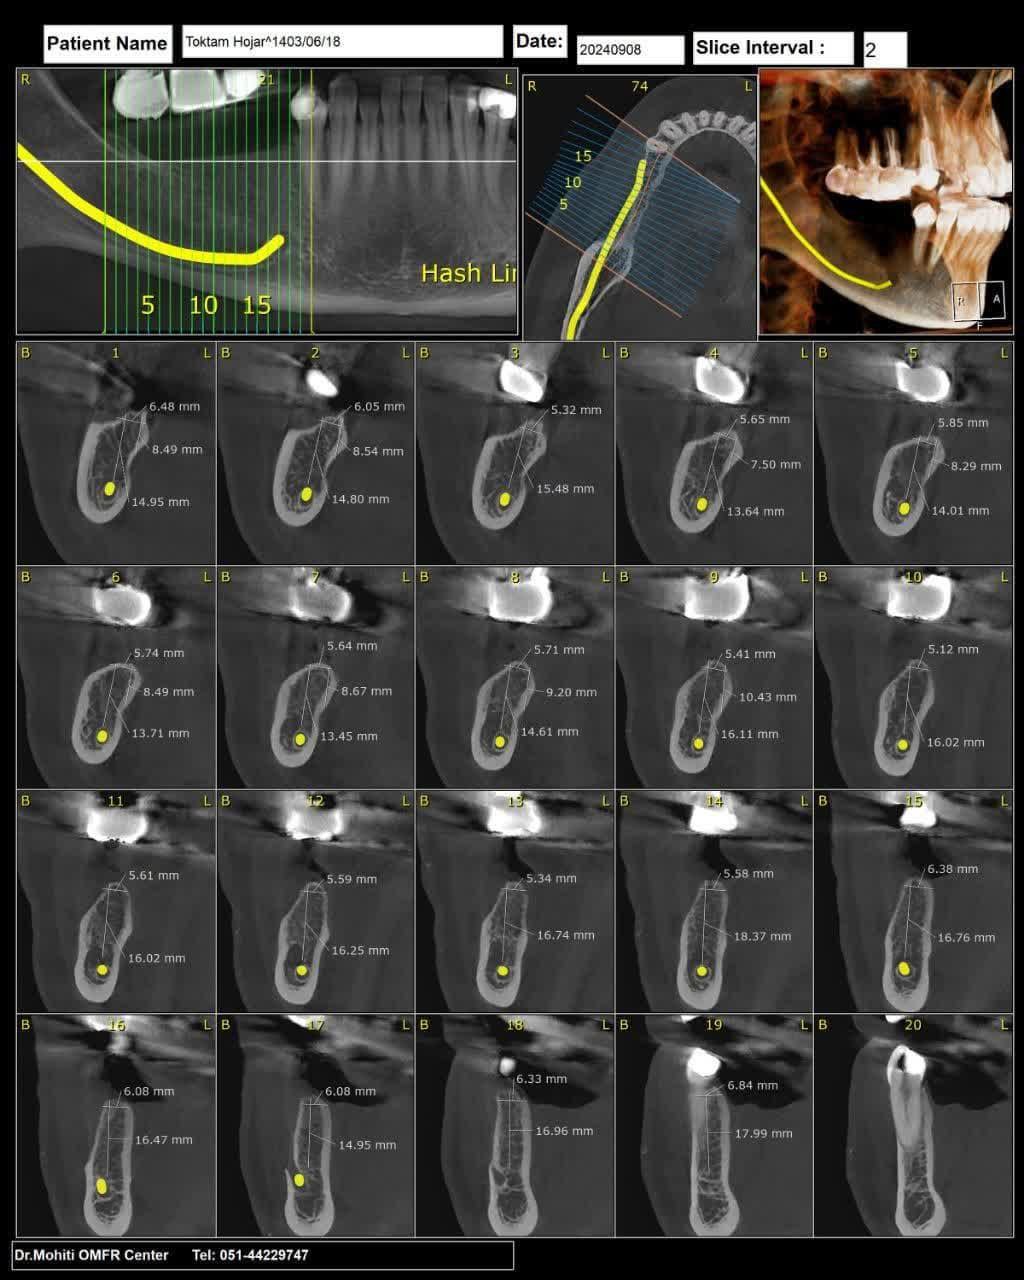

در اين روش ايمپلنت گذاري، ابتدا از بافت داخل دهان با استفاده از اسکنرهاي داخل دهاني، بافت نرم اطراف کامل اسکن ميشود. سپس به همراه سي تي اسکن مربوطه وسايز ايمپلنتهاي تعيين شده به لابراتوار فرستاده ميشود. لابراتوار بر اساس اين اطلاعات يک راهنماي جراحي دقيق براي جراح ميسازد.

سي تي اسکن فک پايين بيمار